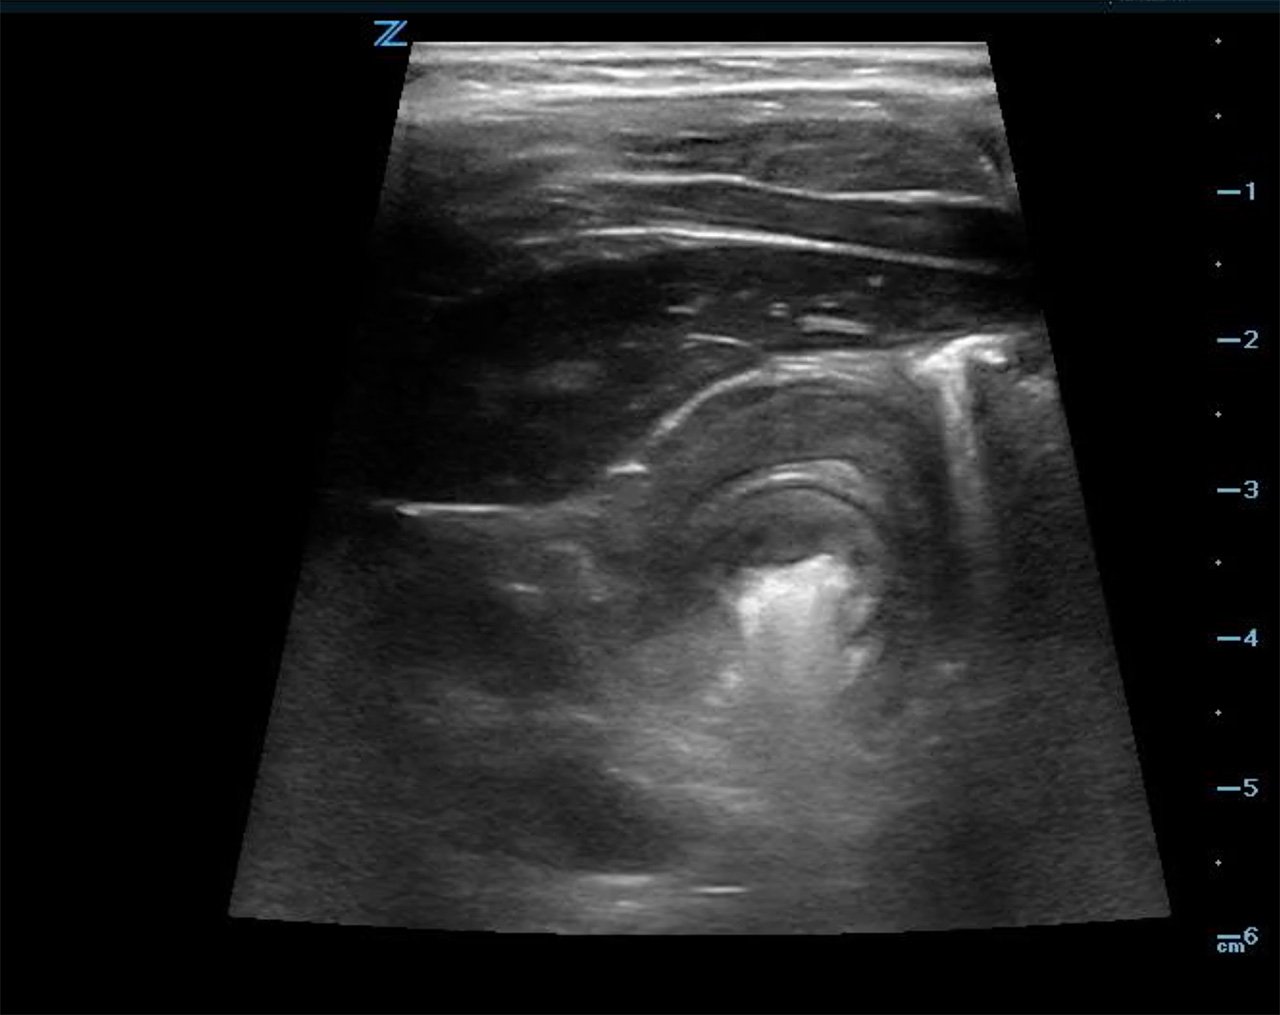

- When the intussusception is seen it should be imaged in both long (Fig. 6a, Video 3) and short (Fig. 6b, Video 3) axis.

- In the long axis, a kidney-shaped mass, which is often called the pseudokidney sign, is seen. This is an oblique view of the invaginated bowel. (Fig. 6a)

- In the transverse axis, a target or doughnut sign, is seen. This is a cross sectional view of a mass made up of invaginated bowel intussusceptum and receiving bowel intussuscipiens, which creates the appearance of concentric rings. (Fig. 6b)

- Figure 6a. Image in long axis of ileocolic intussusception

- Figure 6b. Image in short axis of ileocolic intussusception